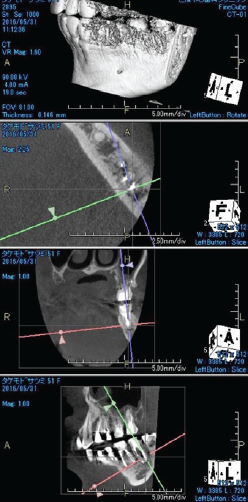

「臼歯部に限局して失活歯が存在し、多発性の根尖病変が認められる症例」

左下大臼歯部の急性炎症を主訴に来院(図16・17・18)。

緊急処置を行い、基礎資料を収集し問題点を抽出し、総合診断治療計画を立案し、患者に説明した。臼歯部に歯科治療が繰り返されている原因の一つに咬頭嵌合位が安定せず、咬合干渉が認められる病的咬合が挙げられる(図19)。臼歯部に応力が集中し、補綴装置やセメントが安定せず歯冠部からの漏洩によって根管内が感染していることも予測できる。包括的な見地から、咬合治療を行うために矯正治療の必要性を説明し承諾を得た。

矯正的診断は上下顎骨劣成長と骨格性開咬を伴うAngleⅡ級症例。矯正治療の目的は前歯の叢生の改善と適正な被蓋関係の確立。治療計画は上顎両側第一小臼歯を抜歯し、上顎前歯の叢生の改善と下顎両側第二小臼歯を抜歯し、下顎両側大臼歯を近心移動し、咬合高径を調整し前歯部の被蓋関係を改善する。初期治療にて炎症のコントロール、主に感染根管の再治療を行い(図20)、矯正治療に入る(図21)。矯正治療により歯のポジションが改善した後、プロビジョナルレストレーションにてリハビリテーションを検証し(図22)、最終補綴処置を行う(図23)。臼歯部の環境が改善された事で、臼歯への力の集中による失活歯の歯根破折の可能性の減少と根尖周囲の歯周組織の安定を確立できた。

<術前左下6・7のレントゲン像>

主訴の歯であり、根尖部に広範囲に渡って透過像を認める

歯質は十分に保存されていることが予測される

(図16)

<左下6・7術前CBCT像>

根尖周囲の骨欠損が著明で舌側皮質骨の開窓も予測される

(図17)

<左下6・7術後CBCT像>

術前のCBCT像と比較して

根尖部周囲組織の再生が確認でき、

歯の保存は可能と判断した

(図18)